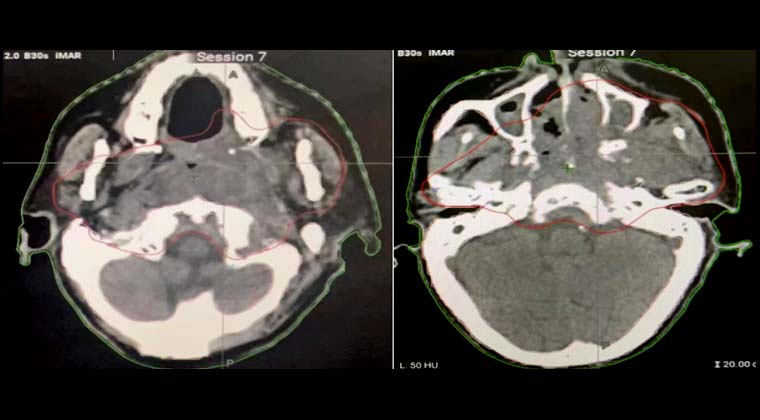

Пациент: мужчина, 66 лет

Злокачественная опухоль носоглотки (недифференцированная некератинизирующая карцинома носоглотки)

С 102021 по 202021 проведена лучевая терапия методом VMAT (PGTV 69,96 Гр / 2,12 Гр / 33 сеанса)

После лечения проводилось непрерывное наблюдение, выявившее постепенное уменьшение опухоли в носоглотке.

При повторном МРТ 002023 отмечено исчезновение опухоли носоглотки и значительное уменьшение лимфатических узлов с ранее положительным диагнозом.

До лечения:

После лечения: